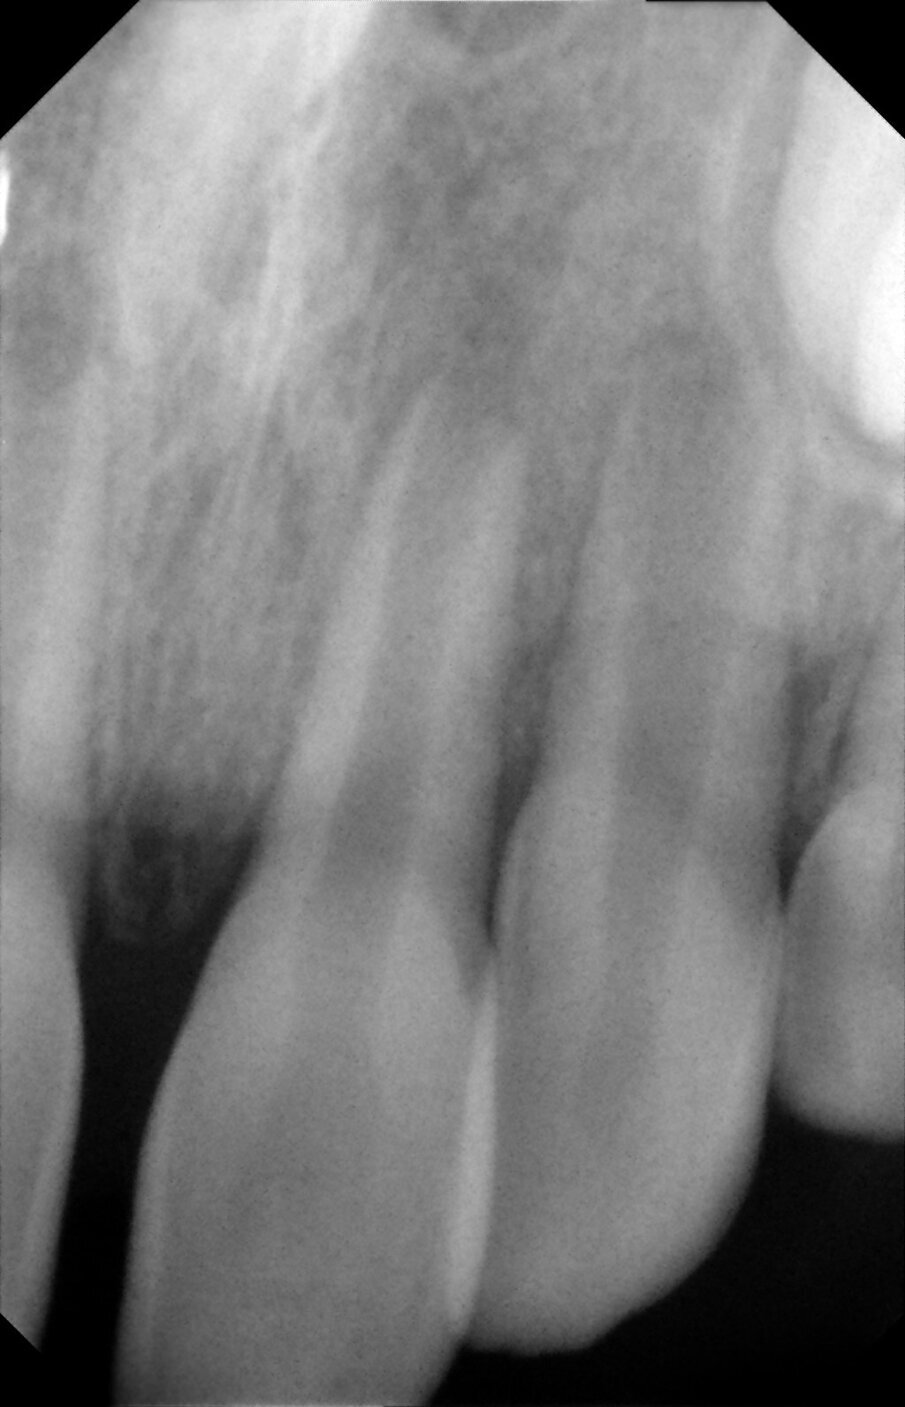

Periapical views of the upper maxillary incisors were obtained to rule out any root fractures (See Figures 4 a & b) revealed immature roots of teeth # 12, 11, 22, no root fractures and an inverted supernumerary apical to 11 and an empty socket of 21. There was no need for soft tissue radiographs as no tooth fragments were missing and the tooth was accounted for.

Figures 4a. Empty socket of 21 due to its avulsion. Notice the immature apices of 12, 11 and 22. In addition there was a supernumerary tooth/mesiodens

Figures 4b. Empy socket of 21 due to its avulsion. Notice the immature apices of 12, 11 and 22. In addition there was a supernumerary tooth/mesiodens